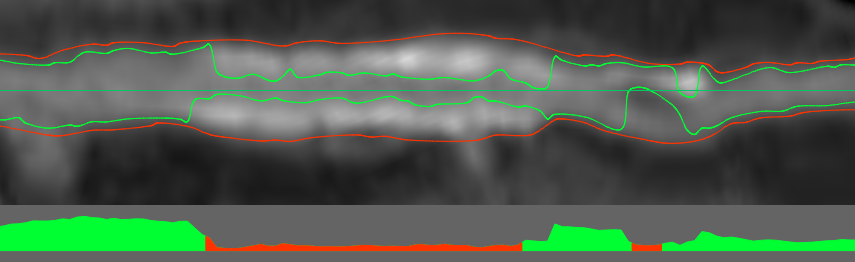

Если визуально отобразить данные согласно порогам, полученным на предыдущем этапе, мы получим такую картину:

Красный цвет — стенка сосуда. Зеленый цвет — просвет. Белый цвет — кальций.

Первое, что бросается в глаза — это “висячий” кальций, который не примыкает ни к одной из стенок. Это считается нормальным и возникает вследствии сглаживания, применяемого самим томографом.